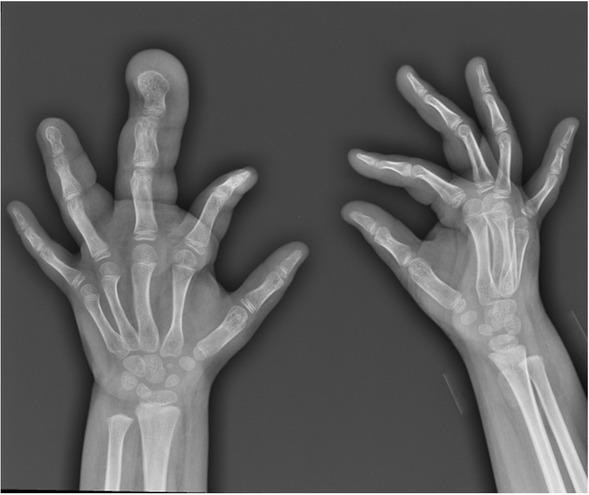

Tissue specimens were obtained during surgical procedures performed for the treatment of macrodactyly. A 5-year-old girl with enlarged left middle and fourth fingers was referred for further treatment at King Chulalongkorn Memorial Hospital (Figure 1).

Figure 1

Clinical and radiologic features of the patient. The radio-graphs show enlarged middle and fourth fingers of the patient’s left hand

The patient was evaluated by physical examination and X-ray imaging, which showed diffuse enlarged soft tissue of left middle and left fourth fingers with abnormal enlarged phalanges (Figure 1). The patient did not have obvious asymmetry of other parts of the body. Initially, the patient underwent the surgical correction to reduce the bulk of left middle finger with fusion of distal interphalangeal (DIP) and proximal interphalangeal (PIP) joints. Physical examination and X-ray imaging 1 year after the surgery displayed re-enlargement of the left middle finger (Figure 2). Fatty tissue debulking, corrective and osteotomy of the DIP joint, and fixation by K-wire were performed in the left middle finger. A surgical complication included a volar pulp flap ischemia. Clinical course of the patient was showed in Table 1.